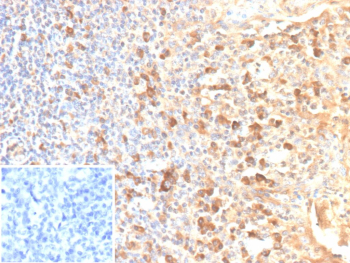

Immunohistochemistry analysis of CD25 / IL2RA antibody (clone rIL2RA/12624) in human tonsil. Formalin-fixed, paraffin-embedded human tonsil tissue shows membranous and cytoplasmic brown chromogenic staining in scattered lymphoid cells, consistent with IL2RA-positive immune cell populations. Inset shows a PBS-only negative control processed without primary antibody, demonstrating minimal non-specific background staining.